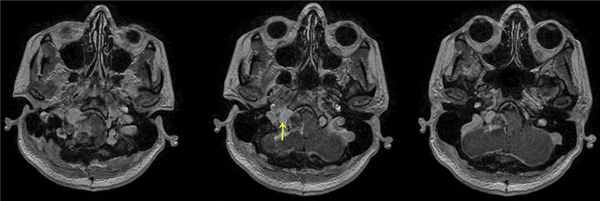

По данным МРТ головного мозга с усилением сигнала парамагнетиком выявлена опухоль парастволовой локализации справа, компримирующая продолговатый мозг и исходящая из расширенного канала подъязычного нерва. Меньший по размерам компонент опухоли располагался в полости канала и распространялся экстракраниально (рис. 1). Рис. 1. МРТ головного мозга пациентки В. до операции. При усилении сигнала выявляется опухоль справа, соответствующая невриноме, в форме «гантели», располагающаяся одной частью на уровне краниовертебрального перехода и вызывающая компрессию ствола мозга, а другой — частью в костных структурах.

При проведении МРТ головного мозга пациентки В. на 3-и сутки после операции выявлена остаточная часть опухоли в канале подъязычного нерва (рис. 5). Рис. 5. МРТ головного мозга пациентки В. на 3-и сутки после операции. При усилении сигнала парамагнетиком определяется остаток опухоли в канале подъязычного нерва справа (указано стрелкой).